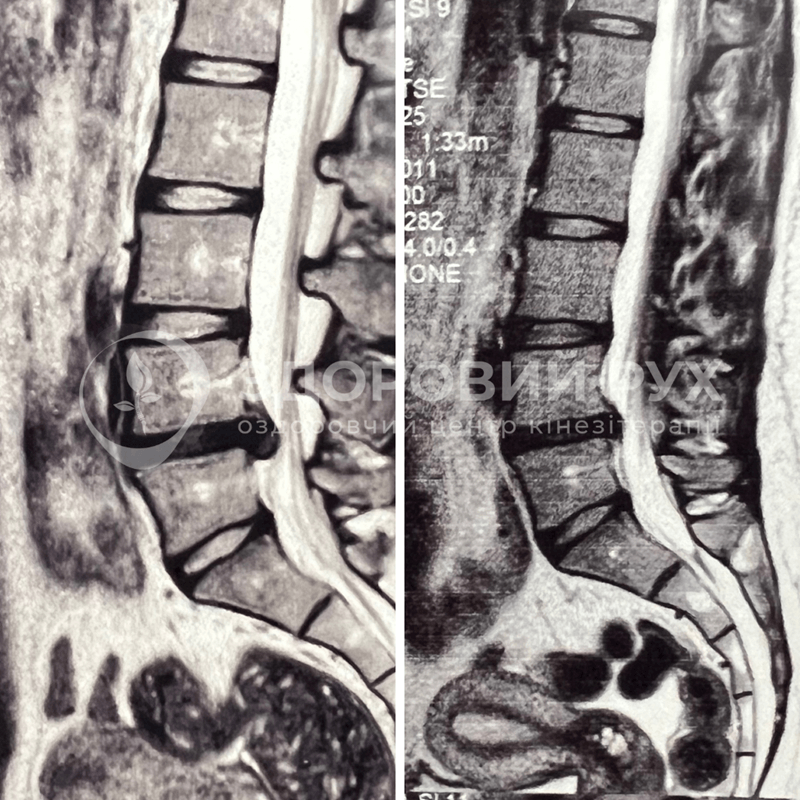

Пацієнтку турбував біль в попереку та по нозі, було важко нахилитися вперед щоб взутися, підняти ліву ногу, через що з’явилася кульгавість. Було неможливо довго сидіти, стояти чи ходити, лікарі рекомендували операцію на грижі міжхребцевого диску.

Але, після 1,5 року занять в нашому центрі, пацієнтка повернулась до активного руху, почала знову нормально ходити, нахилятися та діставати руками до підлоги, а грижа зменшилась майже вдвічі!